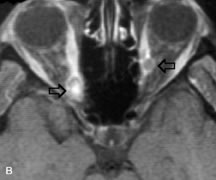

MRI is an excellent modality for demonstrating enlargement of the cavernous sinus and dilation of the superior ophthalmic vein in patients with high-flow carotid-cavernous fistulas (Fig. 14).37MRA may be helpful in the evaluation of the venous outflow pattern. The rapidly flowing blood in these vascular structures carries the excited protons out of the section before they can be imaged, resulting in their dark appearance.5 In low-flow dural arteriovenous malformations, MRA may help define the arterial feeding vessels.45

Fig. 14. Patient with Ehlers-Danlos syndrome who presented with abrupt onset of severe proptosis. A-C. Postcontrast fat-suppressed T1-weighted MR scans demonstrate marked proptosis and engorgement of the extraocular muscles and superior ophthalmic vein (arrows). D. T2-weighted scan through the cavernous sinus demonstrates enlargement and arterialized flow void within the right cavernous sinus (open arrow).